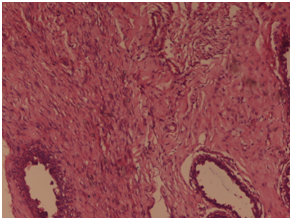

A 50years old female presented to the surgical outpatients department with complaints of painless lump in the left breast for the last 5months. On inspection a swelling was seen in the upper outer quadrant. Skin overlying the swelling appeared to be normal and the nipple was slightly deviated medially. On palpation a hard, painless mass of size 4x3cms was palpated in the breast with irregular margin, fixed to the underlying tissue and attached to overlying skin. Overlying skin showed peau de orange. Left axilla showed no enlarged lymph nodes. On mammography of the left breast, the swelling showed areas of microcalcification. Routine blood investigation showed increased leucocyte count. X-ray of pelvis and spine show no evidence of distant metastasis. On fine needle aspiration cytology, sheets and nests of pleomorphic atypical ductal cells was seen, with nuclear hyperchromasia, increased nuclear cytoplasmic ratio, prominent nucleoli and moderate amount of eosinophilic cytoplasm. A foci of benign spindle cells with wavy nuclear morphology was also seen. Based on the investigations, a diagnosis of infiltrating ductal carcinoma is made and the patient underwent modified radical mastectomy. On histopathology, grossly the tumor was located in the upper outer quadrant measuring 4.5x3x1.5 cm in dimension. A subareolar extension of tumour was seen below the nipple-areola complex measuring 2x1x0.7cm in dimension (Figure 1). Cut section showed a greyish hard solid tumor with areas of haemorrhage and necrosis. Six lymph nodes were also dissected. On microscopy, sheets or whorls of tumor cells was seen with cellular and nuclear pleomorphism, hyperchromatic nucleus and high N/C ratio with prominent nucleoli and moderate amount of eosinophilic cytoplasm (Figure 2). A foci of fascicular pattern of proliferation of peripheral nerves in wavy serpentine configuration and fibroblasts was seen associated with the tumor (Figure 3). Resection margin and nipple areola complex was free from any tumor deposits. Lymph nodes showed only reactive changes. On immunohistochemistry, the foci of nerve proliferation showed diffuse positivity with S100 (Figure 4). A final diagnosis of infiltrating ductal carcinoma with neurofibroma was given. Adjuvant chemotherapy with 6 cycles of Cisplatin (50mg) was administered along with 50G of Co-60 teletherapy. After 12months of follow up, no recurrent disease was noted.

Figure 2 On microscopy, sheets or whorls of tumor cells was seen with cellular and nuclear pleomorphism, hyper chromatic nucleus and high N/C ratio with prominent nucleoli and moderate amount of eosinophilic cytoplasm. Haematoxylin and Eosin x 40X.